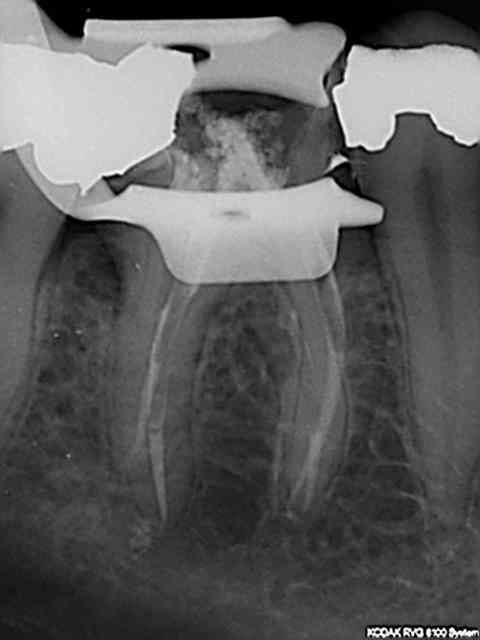

Je m'entraine au mac spaden mais abrès avoir réalisé des bouchons apicaux au friendo ( enfin j'essaye par ce que ca bloque un peu trop loin de l'apex vu que je n'ai pas toutes les tailles d'inserts lol !); Pas franchement de meilleure image qu'au monocone scellé.

Je me fais chier pour rien je pense mais j'appréhende cet engin qui tourne à 40 000 tours ( j'utilise le diametre 40 pour une préparation au R25)

Ca compacte dur par contre vu que l'intégralité du cone ( ici un diametre 40) disparait dans le canal.

En termo-compaction pure à combien de mm de l'apex faut il envoyer l'engin ? vu la pression que ca développe une connerie est vite arrivée.

pas cool de commencer par une 36 de 4 canaux. Par contre.)))))))

En thermocompaction faut se tenir à 4mm de l'apex (a peu pres). Et même si on voit pas tout le temps la différence radiologiquement avec le monocone, on est sur que c'est étanche à l'apex (ce qui est pas du tout le cas avec un monocone scellé...)

Oui c'est la meme chose avec le système B utilisé (friendo de hufriedy). Seulement j'ai pas réussi à descendre les inserts à 4 mm de l'apex (trop gros taille FM/06) curieux d'ailleurs dans certains canaux je n'en suis pas loin. Mon obturation est donc en monocone scellé au bout.)))))

Pour un alésage en 25 /06 quel diametre utiliser ?

Un compacteur de 30. Les revo condensor sont parfait ils ont une bague violette. Je ne me sers presque que de ces thermocompacteurs. La densité des cônes compactes à la radio dépend de leur concentration en eugenol.donc peu significatif. Pour me faire la main je passais le cone puis un.coup de finger spreader et après seulement le compacteur